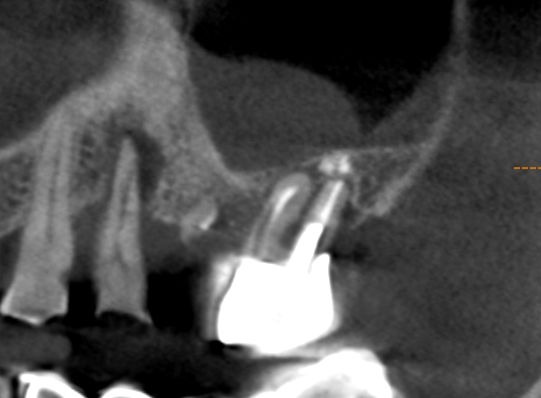

На верхней челюсти у пациента отсутствовали зубы 1.4,1.5 и 1.6. В области зубов 1.7 и 1.8 обширная радикулярная киста, оттесняющая гайморову пазуху. Выполнена цистэктомия с удалением несостоятельных зубов 1.7 и 1.8, заполнение полости кисты остеокондуктивным костным материалом, имплантация в позиции 1.4 и 1.5. Имплантация в области 1.6 и 1.7 будет выполнена после интеграции костного материала